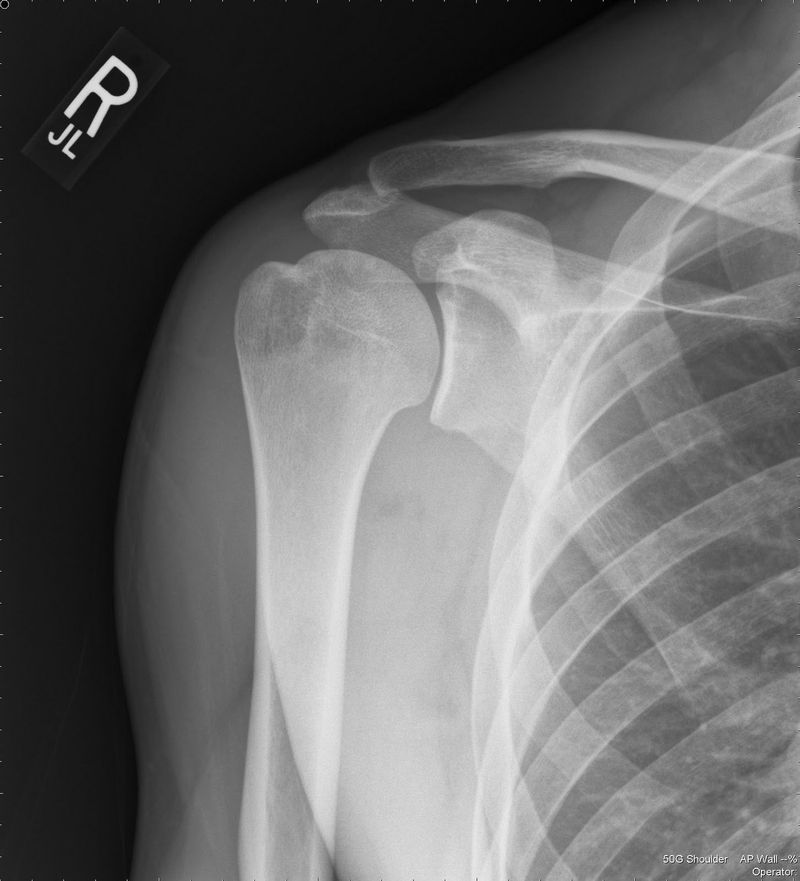

Винтообразный перелом с вывихом.

Normal shoulder joint

It's normal, isn't it?

Appears normal

Lateral veiw might help. Looks normal but i think there is a posterior dislocation as arm is internally rotated

Seems like posterior dislocation of shoulder joint